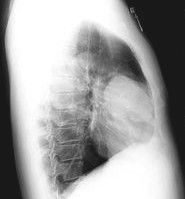

胸腺實驗室檢查可見外周血淋巴細胞計數低於1.2×109/L(1200/mm3),主要是T細胞數量降低。細胞免疫功能檢查:對各種皮膚抗原的遲發性超敏反應陰性,E玫瑰花形成率、PHA淋巴細胞轉化率顯著下降,提示細胞免疫功能低下。體液免疫功能大致正常或略低。血液化學表現為血鈣低,血磷過高,血清甲狀旁腺激素含量很低。X射線檢查不顯示胸腺陰影。

根據典型臨床表現、實驗室檢查、胸部X射線檢查可以確診。組織學上應與繼發性胸腺萎縮相鑑別。後者無論胸腺萎縮到何種程度,鏡下仍可見到哈塞爾氏小體,病因去除後,胸腺改變常可逆。

正側位胸片上見到前縱隔有圓形或橢圓形團塊陰影是診斷本病的主要依據,若同時伴發重症肌無力即可確診。CT掃描有助於檢查腫物的大小和定位。腫瘤的良惡性除組織學上觀察瘤細胞分化的程度外,重要的是術中觀看其有無包膜外侵犯。本病還要注意與其他致胸腺腫大的疾病鑑別,排除前縱隔的一些疾病,如血管瘤、前縱隔轉移瘤、腫大的淋巴結、間皮瘤、甲狀腺和甲狀旁腺腫瘤及嗜鉻細胞瘤等。